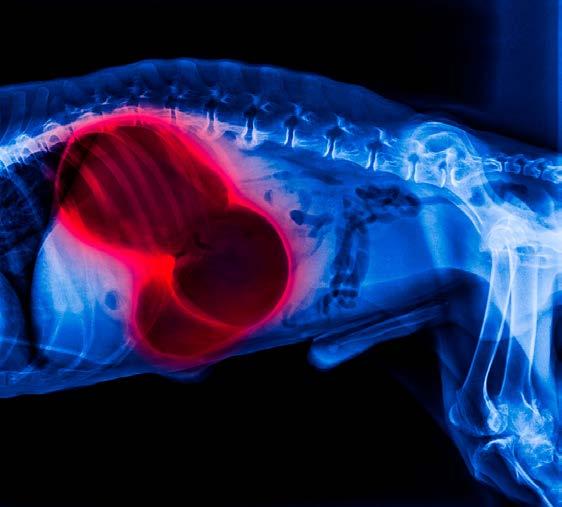

1. REDUCING THE RISK OF BLOAT

One of the most serious health concerns linked to rapid eating is gastric dilatation-volvulus (GDV), or bloat. This is a life-threatening condition in dogs where the stomach fills with gas and can twist. Large and deep-chested breeds, such as Great Danes, Weimaraners, and Setters, are particularly at risk.

While bloat can occur for multiple reasons, eating too quickly is considered a contributing factor. By slowing a dog’s eating pace, slow feeders may help reduce the likelihood of excessive air swallowing (aerophagia) and the subsequent risk of GDV.